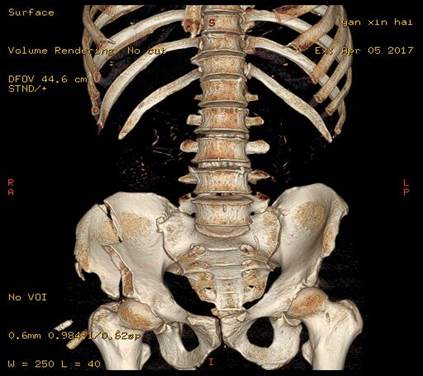

病例三:Tile B1分型,术前CT